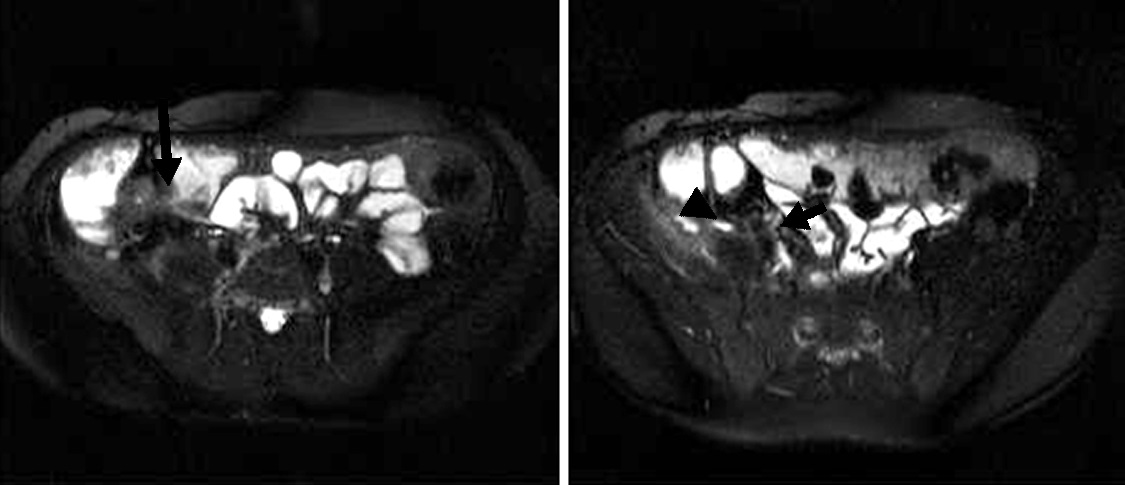

Figura 2

Paciente de sexo masculino de 9 años con antecedente de resección colónica y ostomía por enfermedad de

Crohn. a) Secuencia eco de gradiente coronal donde se idenjpgica el engrosamiento parietal del asa detransitada de

6 mm de espesor (punta de flecha).

b) Misma secuencia muestra adenomegalias ileocólicas de hasta 10 mm como

elemento de actividad (punta de flecha).

c) Secuencia T2 axial con saturación grasa evidencia edema submucoso

como una banda hiperintensa central entre la mucosa y serosa (flecha).